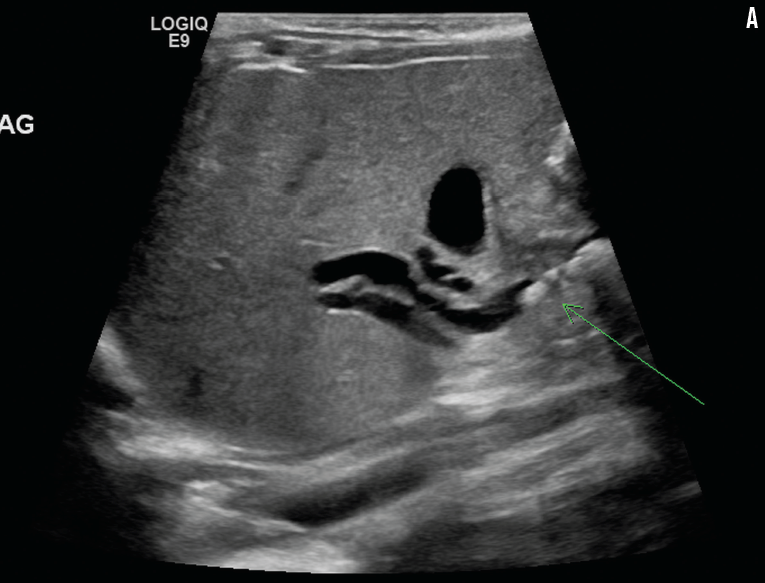

Lisa Bouma, MD; Magda Mendez, MD, FAAP; Sergey Prokhorov, MD; Apeksha Sathyaprasad, MD

A 2-month-old boy was referred to a neurology clinic for a superficial strawberry hemangioma over his lower back.